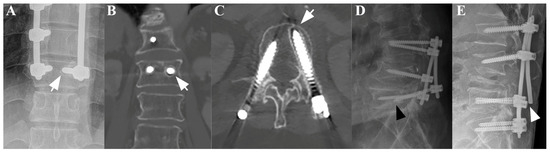

3.1.1. Case 1

3.1.2. Case 2